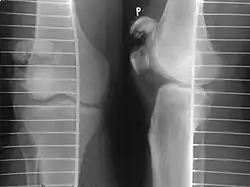

| A fracture of the patella seen on a lateral view | |